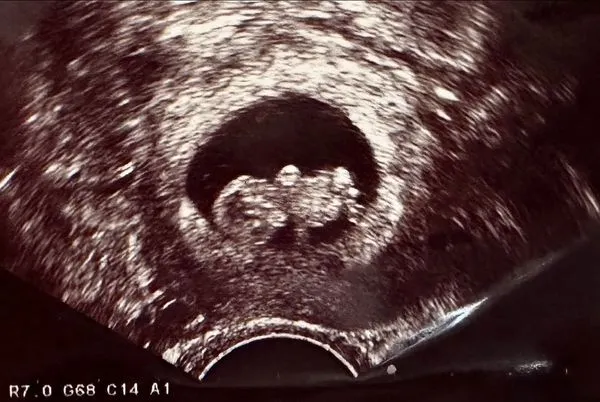

李佳穎高興宣秀超音波照。翻攝李佳穎臉書

李佳穎透露做了9次取卵和2次植入,感路謝在41歲高齡還能順利懷孕,初期因為有過2次大出血,在醫院臥床安胎2個多月,直到現在才感受到幸福的胎動,在肚子變大後,有勇氣和眾人分享這份喜悅,「也希望自己可以平安健康抱在懷裡⋯寶寶,我們年底見。」